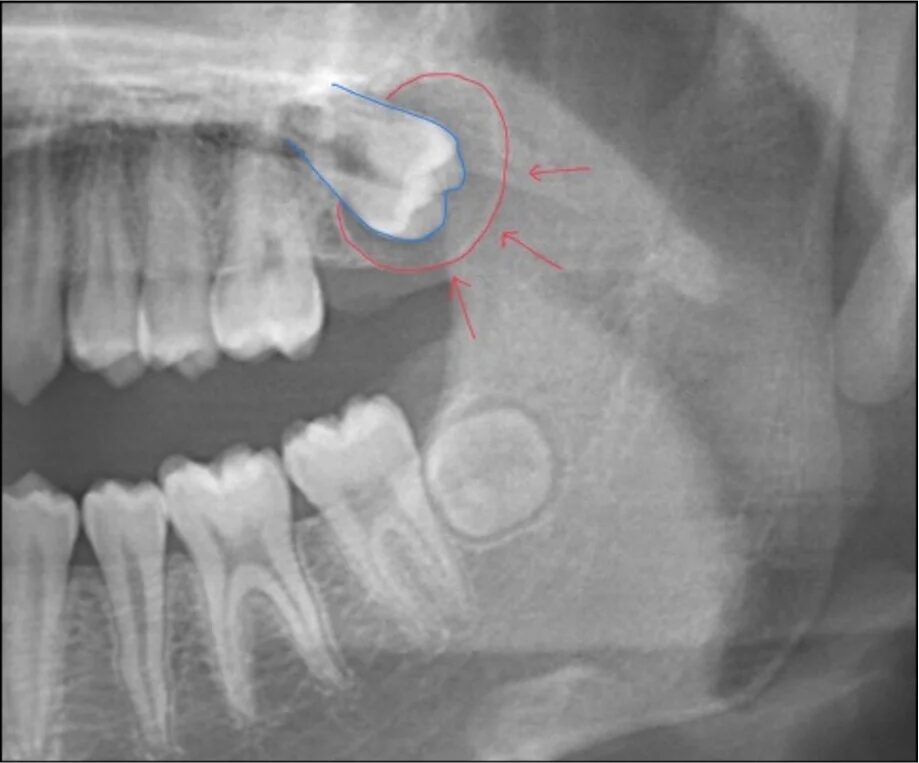

3.腫瘍や嚢胞の原因になっている

親知らずが原因で含歯性嚢胞(がんしせいのうほう)などの嚢胞や腫瘍ができる可能性があります。

• 骨の中に完全に埋まっていて、レントゲン写真上問題が無い場合

その場合は、親知らずの生え方や血管・神経の位置などをCT撮影を行い正確に検査し、安全面に配慮して抜歯します。リスクを伴う場合は、提携先の専門外来をご紹介しますのでご安心ください。